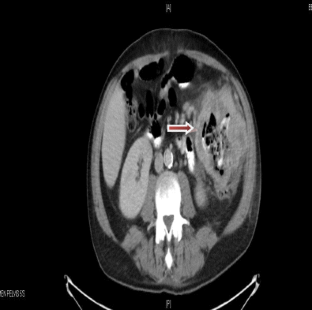

Fig. 1